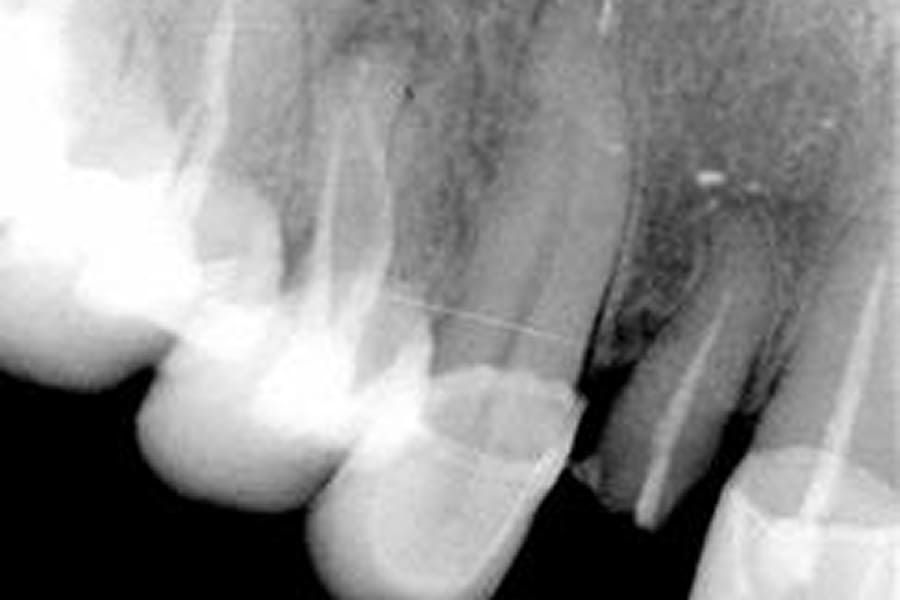

avaliação clínica com radiografias e, quando necessário, tomografia

planejamento conforme a posição e forma da raiz